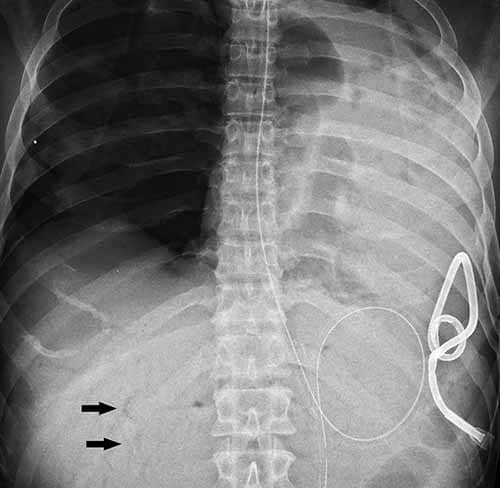

If gas embolism is suspected at autopsy, radiography or CT prior to prosection is strongly encouraged. Scenarios that may suggest gas embolism are recent traumatic injury to the thorax, head, or neck, sudden death following a therapeutic or surgical procedure, and recent delivery of child or abortion. External examination findings supportive of fatal air embolism include subcutaneous emphysema and crepitance. There may additionally be marbling, congestion, and/or petechiae that is particularly prominent superiorly (e.g., in the skin of the face, neck, or chest). Chest radiography is not as sensitive as CT and can appear normal in cases of smaller venous gas embolism; with larger volumes, radiolucency (gas) may be appreciated in the main pulmonary artery, right heart (the so-called “C” sign), and hepatic veins (Figure 24-7). CT, by contrast, affords for detection of even small amounts of gas in soft tissues or anatomic cavities. As decomposition can lead to postmortem gas production soon after death, familiarity with typical postmortem gas distribution patterns and/or gas chromatographic analysis may prove necessary in order to distinguish antemortem gas embolism.